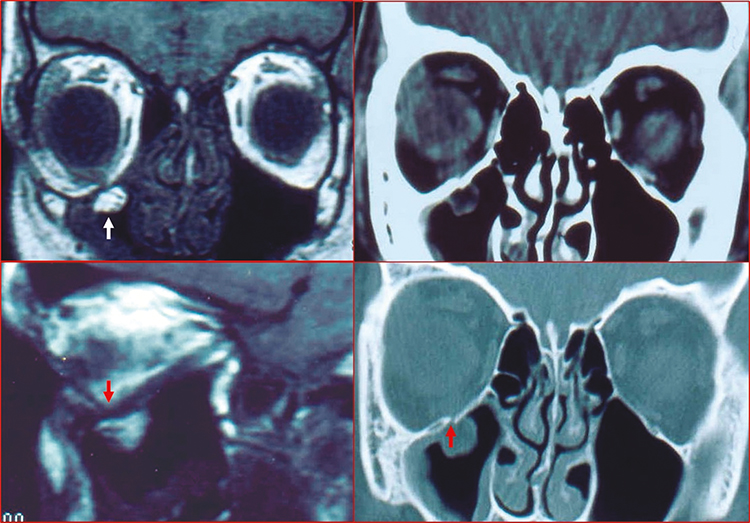

CT of the orbit and midface (axial, coronal, and parasagittal views, 1- to 1.5-mm sections, without contrast) is obtained in all cases of suspected orbital fractures. Bone windows are especially helpful in fracture evaluation (See Figures 3.19.2 and 3.19.3), including the narrow, often-missed white-eyed blowout fracture (WEBOF). Inclusion of the midfacial skeleton is mandatory to rule out zygomatic complex or other midfacial fractures. If there is any history of loss of consciousness, brain imaging is recommended.

Pediatric patients are particularly at risk for a unique type of blowout injury: the trapdoor fracture. Because pediatric bones lack complete calcification, they tend to greenstick rather than completely fracture. This results in an initial fracture, herniation of orbital soft tissue (including EOM) through the fracture site, and rapid snapping back of the malleable bone akin to a trapdoor on a spring. Because of the tight reapposition of the fracture edges, the soft tissue trapped within the fracture becomes ischemic. Children with this type of fracture often have a remarkably benign external periocular appearance but significant EOM restriction (usually vertical) on examination; this constellation of findings has been dubbed the white-eyed blowout fracture (WEBOF). Children may present with a vague history, allow only a limited ocular examination, and be misdiagnosed as having an intracranial injury (e.g., concussion) leading to delay in management of WEBOF. Be aware of the oculocardiac reflex (defined as a heart rate decrease greater than 20% following globe pressure or EOM traction, and can cause nausea or vomiting, bradycardia, syncope, and sweating) that can accompany entrapment. Even in cases where correct orbital imaging is performed, CT evidence of an orbital fracture may be minimal and routinely missed. Careful examination of coronal and parasagittal views is critical in such cases. In typical (i.e., non-WEBOF) orbital fractures, forced duction testing or testing of the dolls eye reflex may be performed if limitation of eye movement persists beyond 1 week and restriction is suspected. In the early phase, it is often difficult to distinguish soft tissue edema or contusion from soft tissue entrapment in the fracture. See Appendix 6, Forced Duction Test and Active Force Generation Test. |